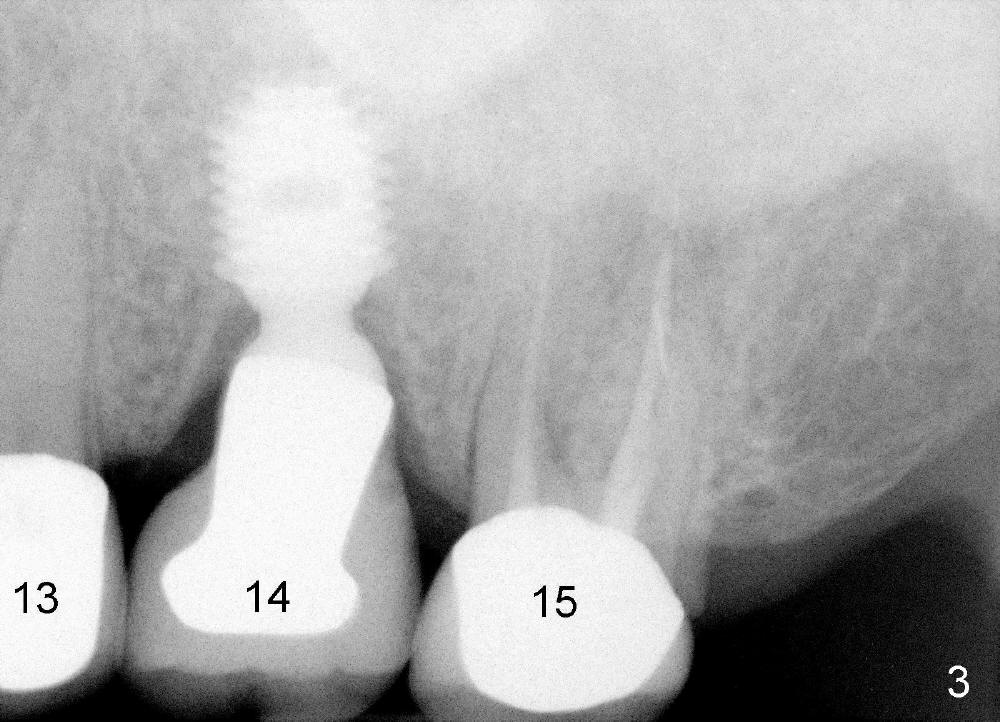

A 71-year-old male is a bruxer. His upper left fixed partial denture was lost 4 years ago (Fig.2). It is replaced by an implant (Fig.3: #14) and two single unit crowns (#13,15). One year later, the tooth #5 is replaced by an immediate implant due to crown fracture (Fig.1,4). Six months after the cementation of #5 implant crown, the tooth #15 is restored by an immediate implant due to root fracture (Fig.6). Recently, porcelain chips off the PFM crown of #13. The patient finally agrees to have another implant (Fig.1: #2) to make his dentition complete and distribute masticatory force more evenly.

The advantage to place implants for a bruxer is that there is sufficient bone height (Fig.2-4). The bone density also appears to be high; there is a thick cortical bone in the edentulous ridge of #2 (Fig.4 arrowheads). Incision will be made; suture may be required for flap fixation. Osteotomy is initiated by 2 mm pilot drill 4 mm from the neighboring tooth (Fig.5); the depth is 8 mm. The depth of the osteotomy is adjusted according to X-ray taken with a parallel pin. Sinus lift may be needed (Fig.5 dashed line: sinus floor). The density of the cancellous bone will be felt and determined while using the 2 mm pilot drill for initial osteotomy. If the density is high, Bicon reamers will be used for further osteotomy and bone saving. Otherwise, osteotomy will be finished mainly with Bone Expander Kit or osteotomes. Bone-level implant is used, followed by a healing abutment. Decortication will be done with a surgical handpiece with a fissure or round bur. If no suture is used for flap fixation, perio glue will be used to close the incision without perio dressing. If the wound is not approximated each other well with sutures, perio glue can be used for complete seal.